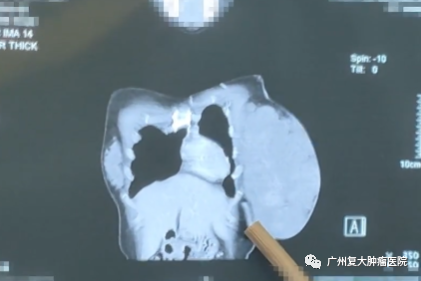

入院完善相关检查后发现,婷婷的左乳区域皮肤局部橘皮样变,可扪及25×20cm大小肿物,穿刺活检结果显示为:乳腺腺病伴纤维腺瘤形成,未见癌。

结合检查结果,我院专家开展复杂病例讨论,一致认为婷婷乳腺肿物巨大,但皮肤及胸大肌未见明显粘连侵犯,不排除良性肿瘤可能,有手术指征,建议术中冰冻明确诊断,若为良性,则进行左乳肿物切除术,若为恶性,则实行改良根治术。

所幸术中快速病理回报未见恶性。一切依计划进行,医生仔细分离肿瘤以及周围正常组织,游离皮瓣,顺利将肿瘤组织切除,解除了患者的巨大肿瘤负荷。切除的巨大肿瘤标本足有6斤重,大小约23×16×12cm,婷婷开玩笑说,这肿瘤可比我小孩出生还要重。